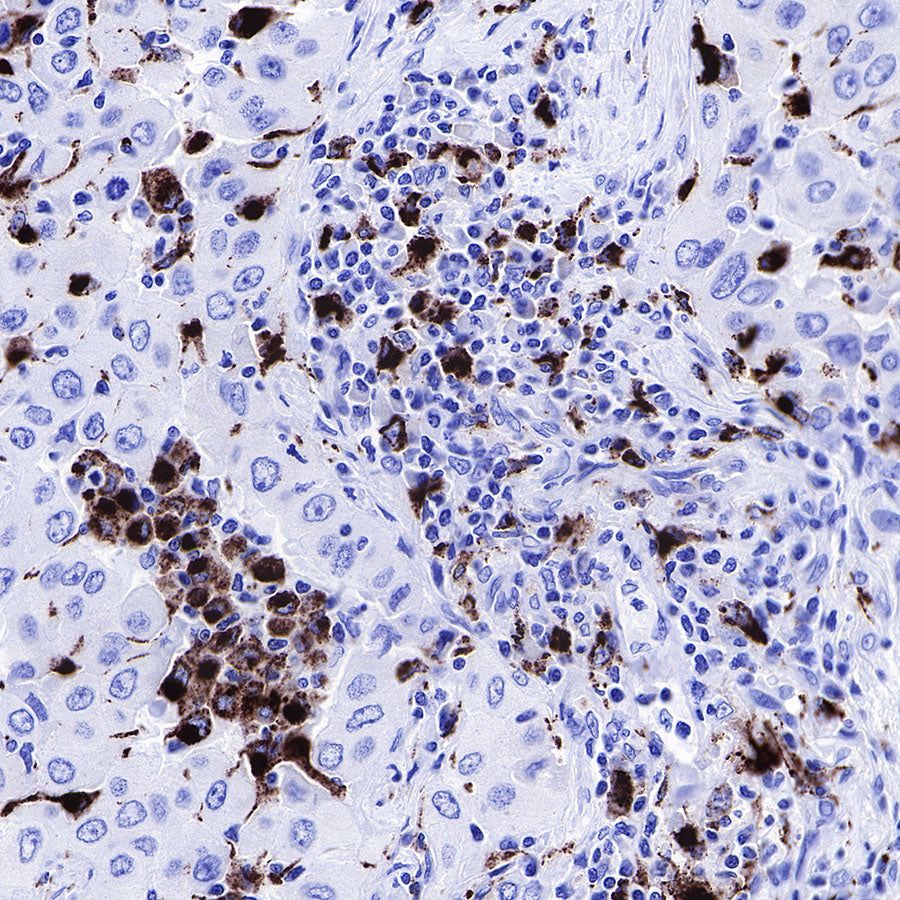

IHC shows positive staining in paraffin-embedded human lung adenocarcinoma. Anti-CD68 antibody was used at 1/1000 dilution, followed by a HRP Polymer for Mouse & Rabbit IgG (ready to use). Counterstained with hematoxylin. Heat mediated antigen retrieval with Tris/EDTA buffer pH9.0 was performed before commencing with IHC staining protocol.